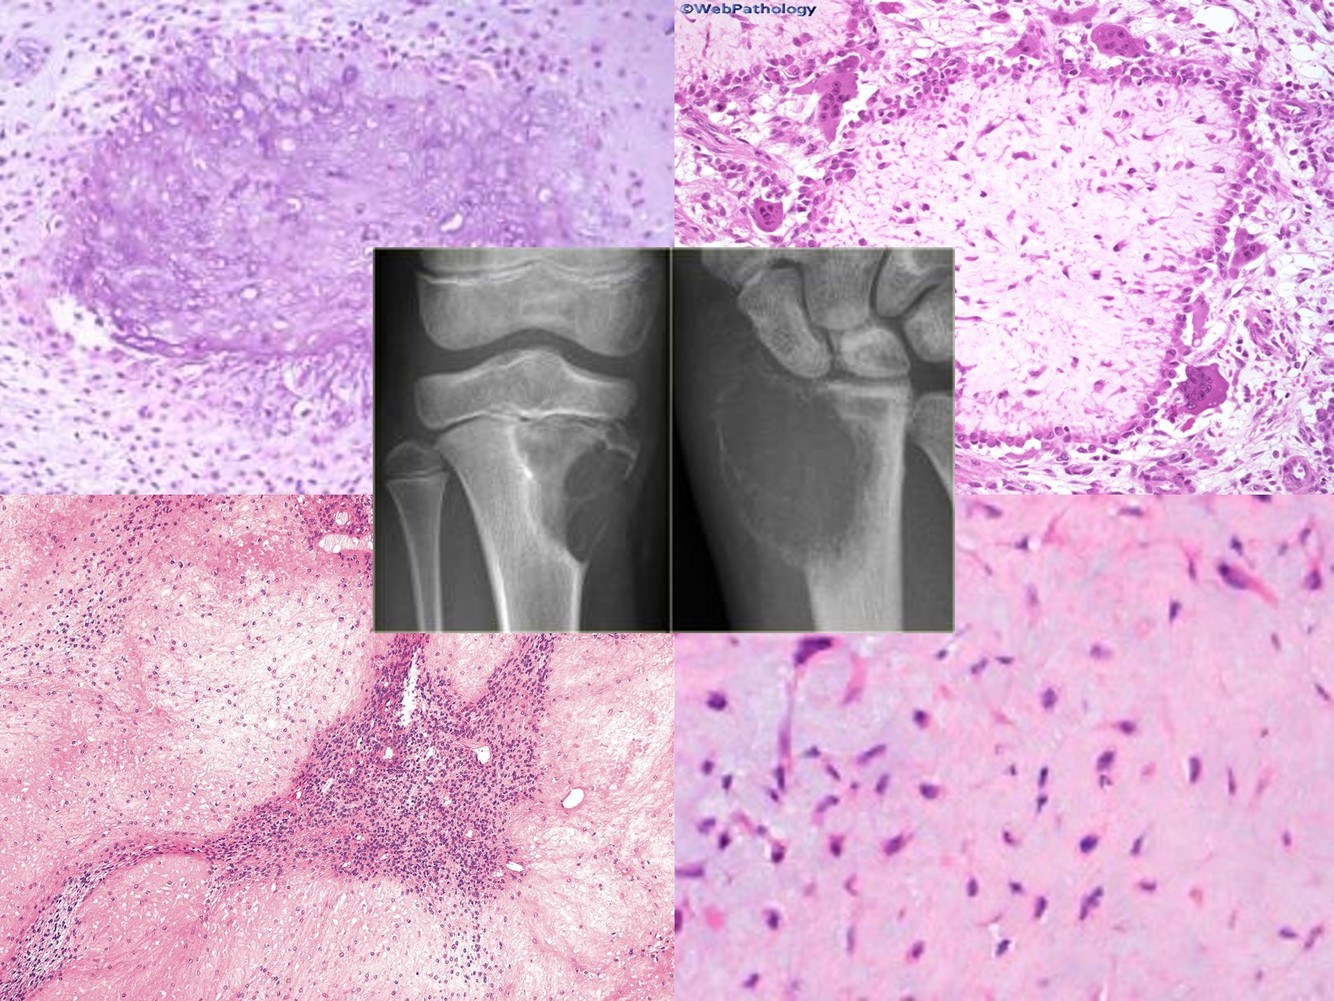

CONVENTIONAL CHONDROSARCOMA

SECONDARY CHONDROSARCOMA

DEDIFFERENTIATED CHONDROSARCOMA

CLEAR CELL CHONDROSARCOMA

MESENCHYMAL CHONDROSARCOMA